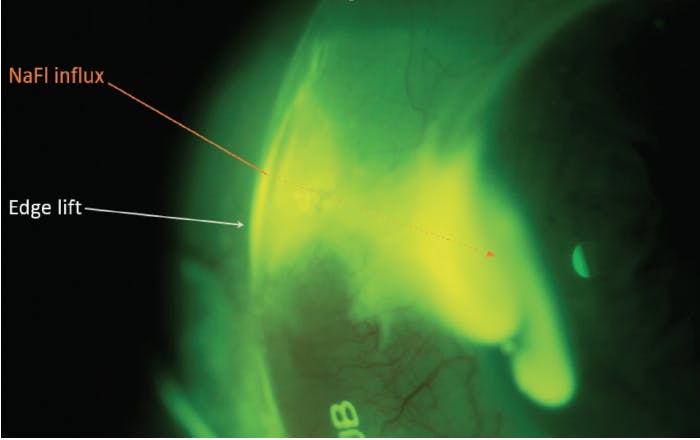

Edge lift or loose haptics can allow more rapid influx of debris into the tear reservoir. Evaluate for sources of debris influx with fluorescein with the scleral lens in place (Figure 4). Consider using toric peripheral curves to best align the haptics to prevent more rapid onset of MDF.

Mechanical irritation from an ill-fitting or flat-fitting haptic can also exacerbate papillary reactions, worsening allergic symptoms.5